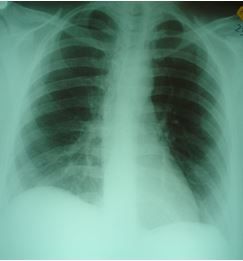

Pain has a wide variety of presentations, often making the diagnosis a significant challenge. Test your knowledge of signs and symptoms in this week's photo quiz.